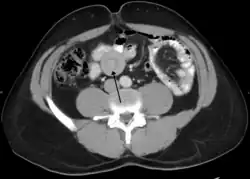

| An intussusception as seen on CT | |

An intussusception is often suspected based on history and physical exam, including observation of Dance's sign. A digital rectal examination is particularly helpful in children, as part of the intussusceptum may be felt by the finger. A definite diagnosis often requires confirmation by diagnostic imaging modalities. Ultrasound is the imaging modality of choice for diagnosis and exclusion of intussusception, due to its high accuracy and lack of radiation. The appearance of target sign (also called "doughnut sign" on a sonograph, usually around 3 cm in diameter, confirms the diagnosis. The image seen on transverse sonography or computed tomography is that of a doughnut shape, created by the hyperechoic central core of bowel and mesentery surrounded by the hypoechoic outer edematous bowel.[10] In longitudinal imaging, intussusception resembles a sandwich.[10] It is also called "pseudokidney" sign because hyperechoic tubular centre is covered by a hypoechoic rim producing a kidney-like appearance.[11]